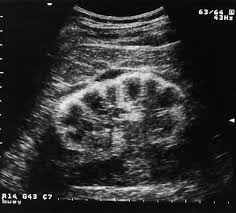

Kidney Ultrasound For Baby. A doctor can then determine whether treatment is necessary. Doctor s monitor the kidney throughout pregnancy with frequent ultrasounds and then recheck the kidney after the baby is born.

This procedure may also be used to determine blood flow to the kidneys through the renal arteries and veins. But i went to mr google and now i am a little big worried. Ultrasound examinations are often done as part of prenatal care.

A doctor can then determine whether treatment is necessary. Kidney fluid in baby ultrasound. What is a kidney ultrasound. This test allows the doctor to examine babies before they are born.